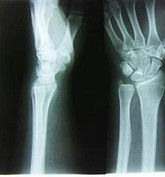

影像學評估

(1)X線檢查評估橈骨遠端損傷的首選檢查。多數骨折、脫位、力線不良、靜態不穩定等,都很容易從標準的x線檢查鑑別。標準的前後位及側位X線可測量出橈骨遠端的掌傾角、尺偏角和橈骨高度等重要參數。